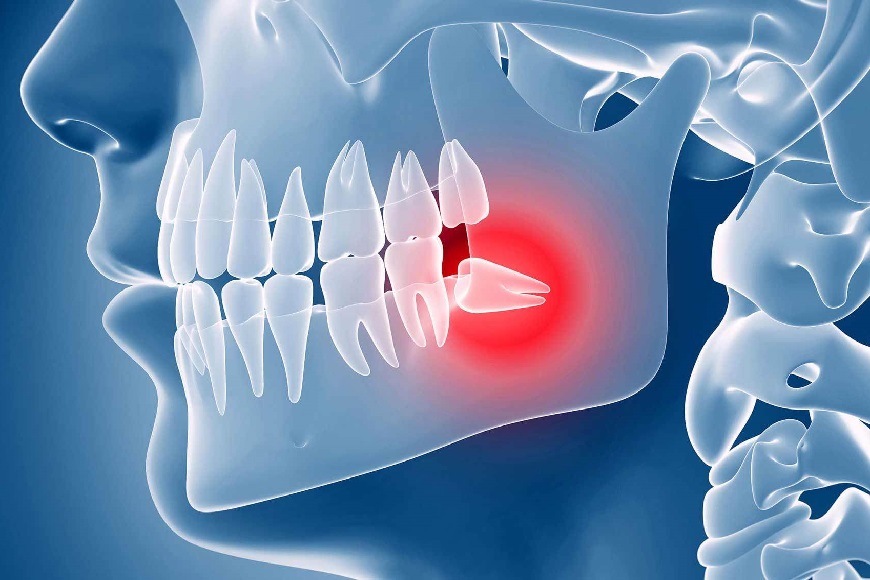

• Malocclusioni causate dai denti del giudizio. Sviluppati possono ostacolare anziché aiutare la masticazione, affaticando l’articolazione temporo-mandibolare. Non sviluppati creano squilibrio tra le arcate, tensioni, dolori e nevralgie dovute allo sforzo compensativo dei muscoli e delle ossa facciali.